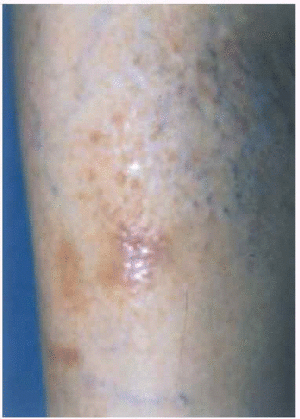

Una biopsia de la lesión cutánea mostró en la tinción con hematoxilina-eosina (fig. 2), un epitelio con una zona de intensa hiperqueratosis, acantosis y papilomatosis con algún cuerpo coloide aislado. En dermis papilar se observaron pequeños depósitos, bien delimitados de una sustancia amorfa, acidófila que daba reacción metacromática con el cristal violeta (fig. 3) y era positiva para rojo Congo (fig. 4). En esa misma zona se observaron incontinencia de pigmento.

Fig. 4.--Sustancias en dermis papilar rojo Congo positiva.

Con el diagnóstico de liquen amiloide, el paciente fue tratado con corticoides de alta potencia (propionato de betametasona), y se logró la remisión completa de sus lesiones cutáneas en un plazo de 3 meses, sin presentar lesiones residuales.